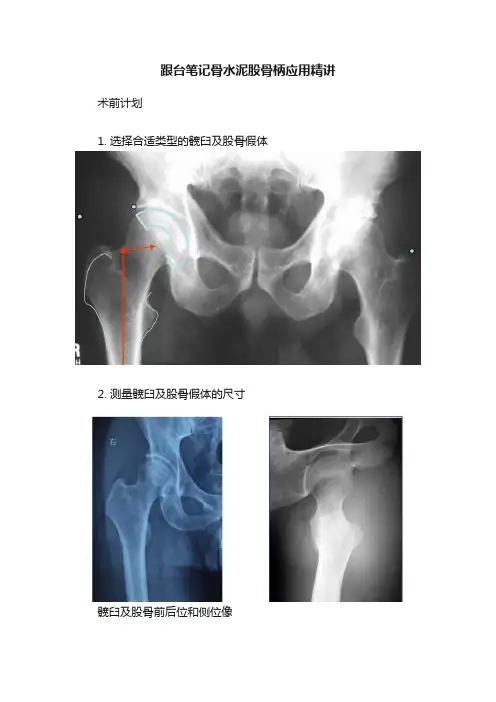

跟台笔记骨水泥股骨柄应用精讲术前计划1. 选择合适类型的髋臼及股骨假体2. 测量髋臼及股骨假体的尺寸髋臼及股骨前后位和侧位像3. 决定是否需要纠正腿长4. 发现并预防手术中可能产生的风险手术操作Part 1.髓腔开口髓腔开口:靠外侧和后侧Part 2.确定前倾角Part 3.建立髓腔通道Step 1•通用铰刀开髓•保持中立位,紧贴大粗隆外侧建立髓腔通道Step 2•为保证正确对线,髓腔锉应靠近外侧、近大转子。